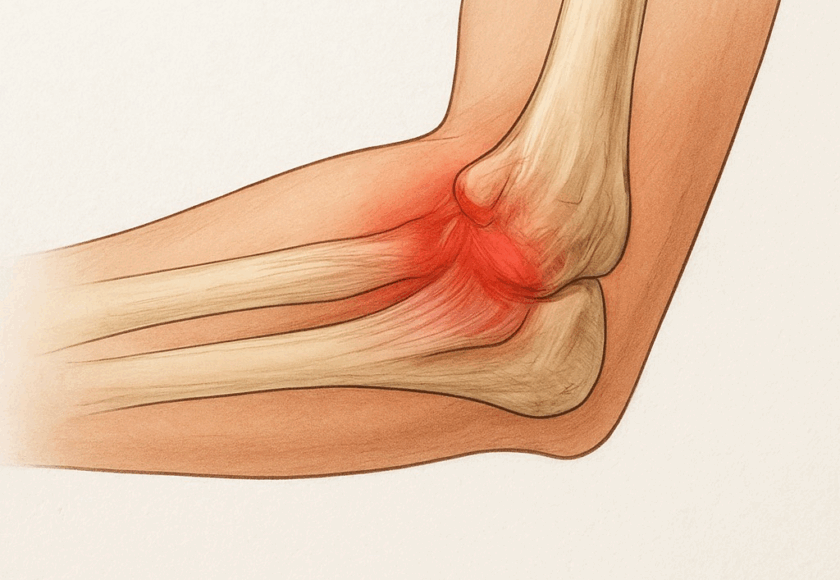

野球肘は「投球障害肘」とも呼ばれ、肘の内側・外側・後方に繰り返しストレスが加わることで起こる障害の総称です。成長期の子どもから大人の選手まで幅広く発症し、早期のケアが将来の肘の健康を左右します。

投球動作の際、

• 内側(牽引ストレス):靱帯や骨端部に強い引っ張り力 → 内側側副靱帯損傷、内側上顆炎、リトルリーグ肘

• 外側(圧迫ストレス):上腕骨小頭と橈骨頭の衝突 → 離断性骨軟骨炎(OCD)

• 後方(衝突ストレス):肘の伸展時に骨同士がぶつかる → 肘頭疲労骨折や後方インピンジメント

というように部位ごとに異なる障害が生じます。特に成長期は骨端線が弱いため、靱帯よりも骨にダメージが出やすいのが特徴です。